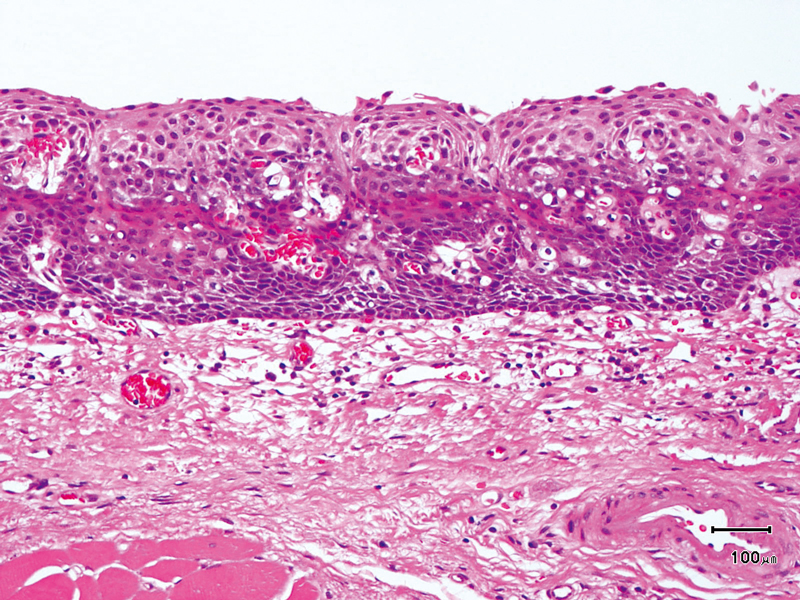

The lesion was detected in the oropharyngeal posterior wall in a laryngopharyngoscopic NBI examination during follow-up after treatment of a carcinoma in the floor of the mouth.

It was recognized under NBI as a lesion with a brownish area, and the close-up view additionally showed scattered brown dots. In the conventional white light image, the same area was seen as a reddening lesion.

The lesion was 5 x 3 mm and located on the back of the soft palate, and was diagnosed as a carcinoma in situ.